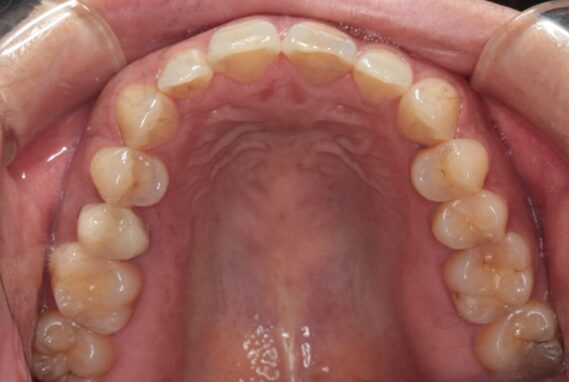

48歳女性